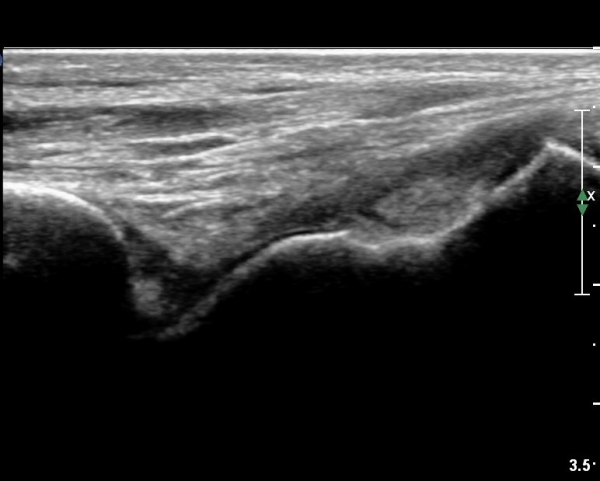

Àü°Åºñ Àδë Á¾´Ü¸é°Ë»ç¿¡¼­ Àü°ÅºñÀδëÀÇ ÆÄ¿­ÀÌ °üÂûµÇ°í(»çÁø 6,7)

ºÎÇÏ°Ë»ç ½Ã °Å°ñ°ú ºñ°ñÀÌ  °úµµÇÏ°Ô ¹ú¾îÁö´Â °ÍÀÌ °üÂûµÈ´Ù(÷ºÎµ¿¿µ»ó 2)